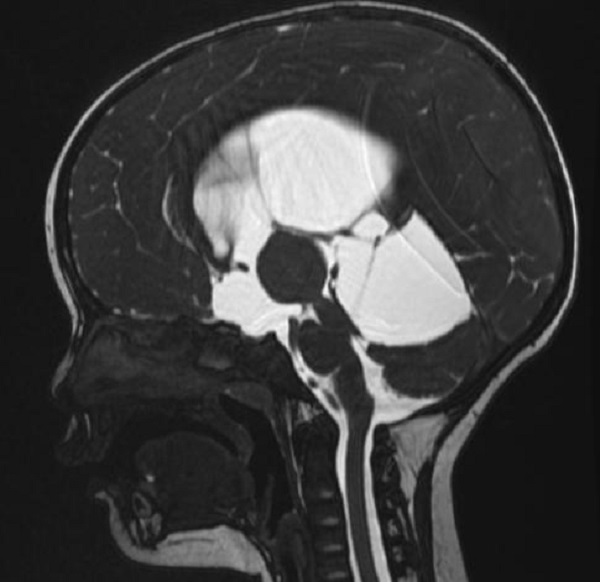

一岁多的赫赫小朋友自出生头颅就比同龄小孩大,近半月来进食后出现呕吐,伴头痛,在当地医院及省内多家医院治疗不见好转,于是来到二一五医院神经重症监护室,因患儿近半月多不能正常进食,入院时精神萎靡,头颅MRI检查提示“脑室系统扩大,双侧脑室额角周围间质水肿,左侧丘脑占位病变,鞍上池及小脑上池扩大”。

为进一步鉴别脑积水类型,行磁共振3D FIESTA序列检查可见侧脑室扩大明显,中脑导水管中段阻塞、三脑室底受压下陷,诊断梗阻性脑积水。